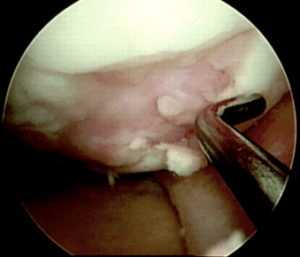

Далее осуществляется артроскопический доступ к мыщелку бедренной кости с поврежденным участком хряща. Производится очистка участка кюреткой и иссечение краев для получения ровного здорового контура. Затем вводится зонд с метками — с его помощью измеряют точный размер дефекта. Если дефект слишком большой или расположен очень далеко, операцию делают с помощью артротомии (открытым доступом).

Следующим этапом делают разрез тканей и получают доступ к тому участку кости, откуда будут брать трансплантат. Используется перекрестный принцип: если восстанавливают дефект на медиальном мыщелке, то трансплантат берут с боковой поверхности латерального и наоборот. Забор ткани осуществляется трубчатым долотом. Очень важно в момент “вбивания” долота сохранять точную перпендикулярность по отношению к поверхности хряща.

После получения необходимого количества костно-хрящевых фрагментов выполняется сверление первого “посадочного гнезда” на дефектном участке хряща. Осуществляется это также трубчатым долотом, но диаметр его на 1 мм меньше того, которое применялось для извлечения трансплантатов. Длина посадочного отверстия измеряется, под него подгоняется длина трансплантата, который осторожно фиксируется на предназначенное для него место способом press-fit. Процедуру повторяют необходимое количество раз. При этом отверстия сверлят таким образом, чтобы они были не параллельны и расходились веером от гипотетического центра кривизны мыщелка, это позволяет максимально точно восстановить кривизну суставной поверхности.